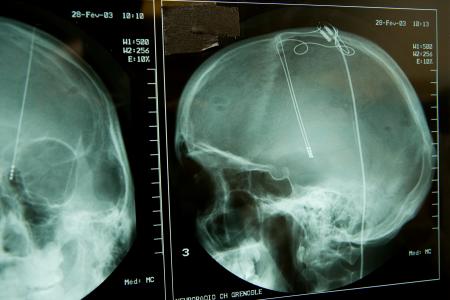

La DBS consiste à implanter des électrodes dans le cerveau à des endroits spécifiques. Ces électrodes délivrent ensuite des signaux électriques qui permettent d’atténuer les symptômes de troubles cérébraux tels que la MP. La DBS conventionnelle fournit un niveau de stimulation constant et peut également entraîner des effets secondaires indésirables, car le cerveau n’a pas toujours besoin de la même intensité de stimulation.

L’aDBS, en revanche, qui utilise des données prélevées directement dans le cerveau du patient et qui, grâce à l’apprentissage automatique permet d’ajuster le niveau de stimulation en temps réel et en fonction des besoins du patient au fil du temps, délivre la juste dose de stimulation.